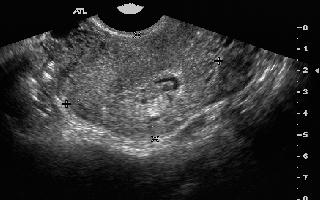

This "endometrial mass" was diagnosed

as placental tissue by pathology at the time of

D&C. Interestingly, this patient was afebrile

and had no symptoms of retained products of

conception. More amazing is the fact that this

patient was 8 months post-partum at the time of

the sonogram!!